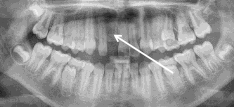

Zojuist heeft de orthodontist vaste apparatuur in je mond geplaatst. Als je in de spiegel kijkt, zie je dat op elke tand een bracket (slotje) is geplakt. Om sommige kiezen zit een metalen band (ring) met aangelaste buisjes. Door de brackets en de buizen heen loopt de boog (draad), die vastzit met kleine elastiekjes of metalen draadjes aan de bracket.